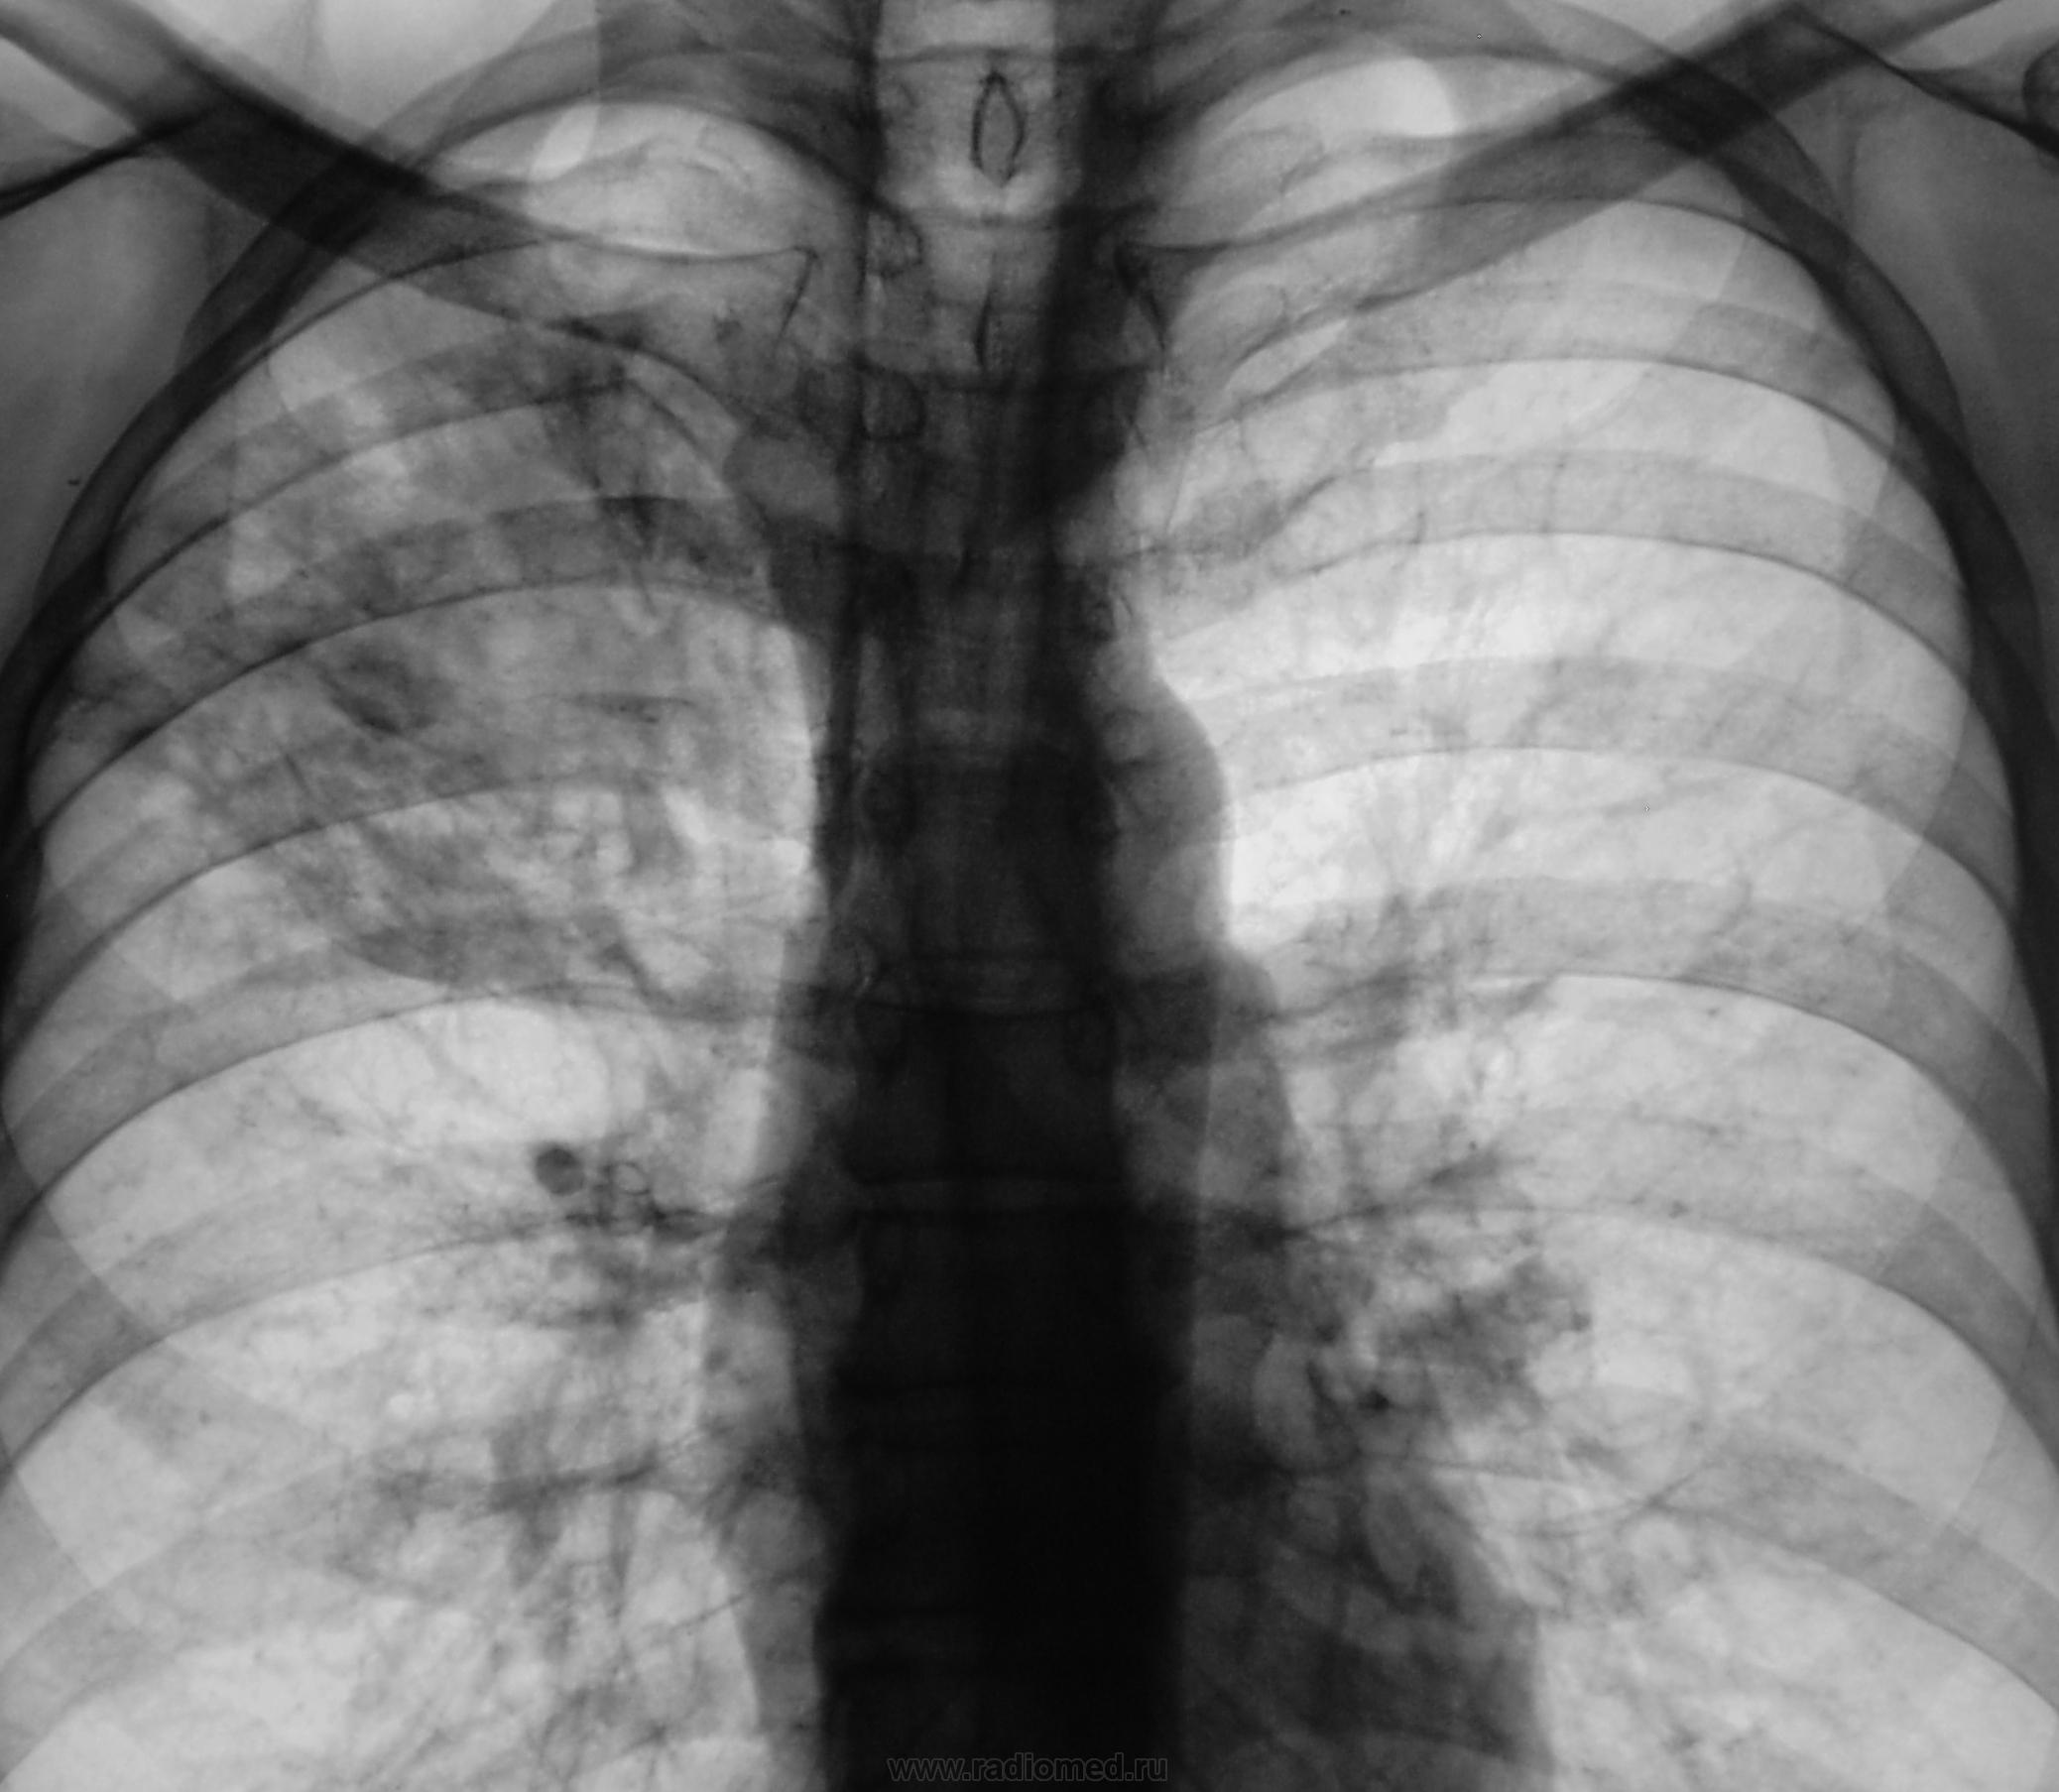

А, через 6 месяцев стало так...

Приложения:

1.p1190042.jpg2.p1190043.jpg3.p1190044.jpg4.p1190045.jpg5.p1190045a.jpg

Мы, после этого дообследования (последнего) упаковали пациента в ОПТД, там взяли, обнаружили палки и пациент начал лечиться